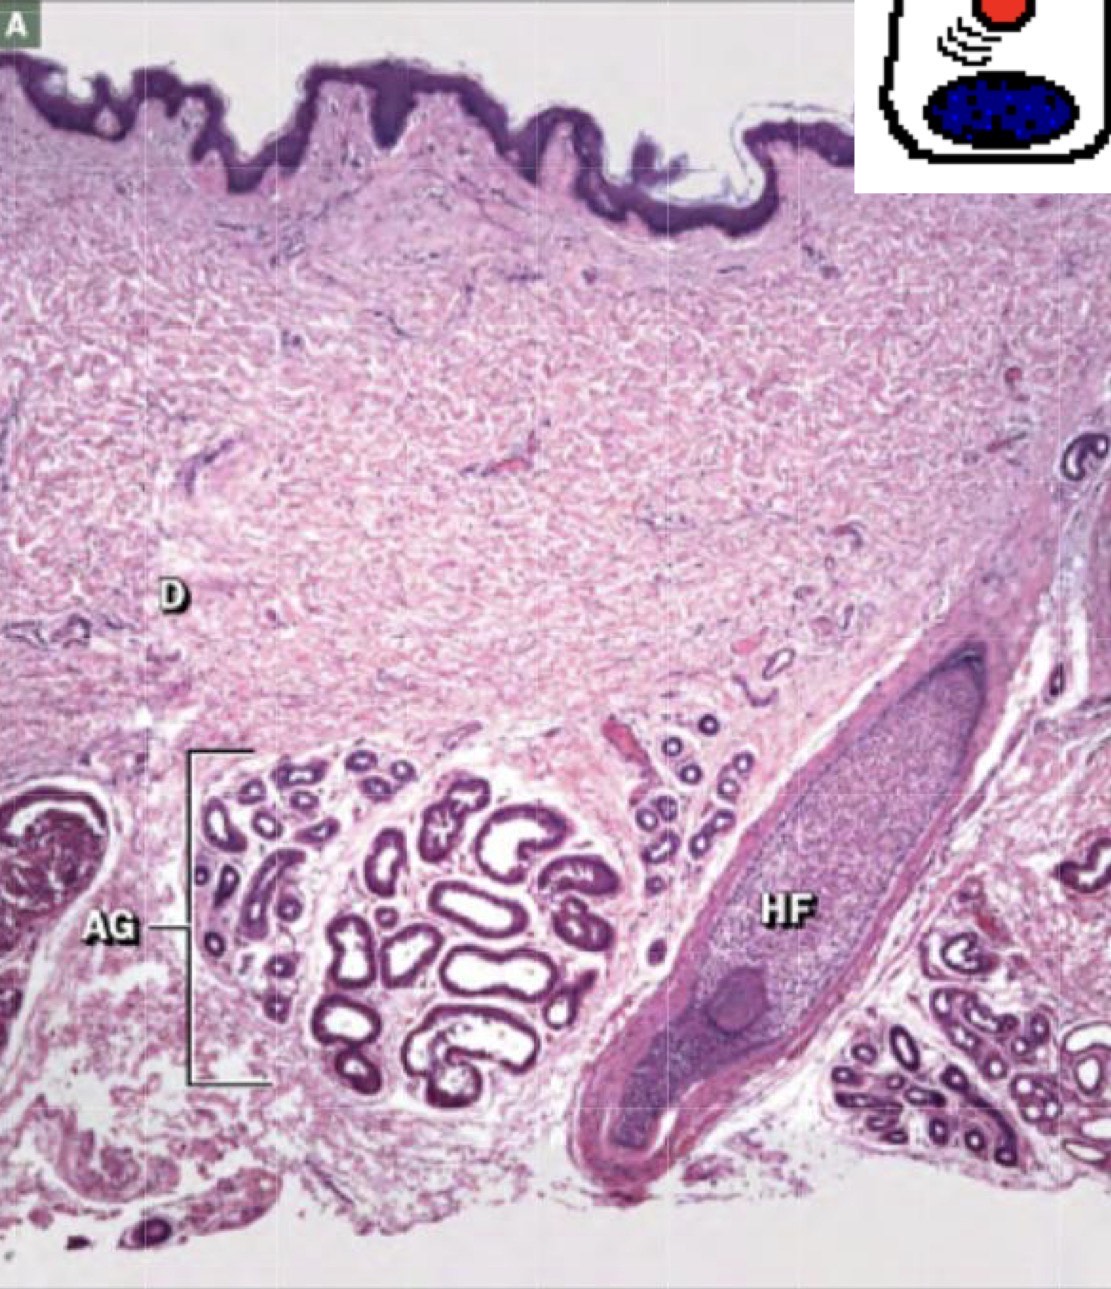

Identify the Structure

1 = Sebaceous gland

2 = Arrector pili M

3 = Hair foll

4 = Sebaceous gland